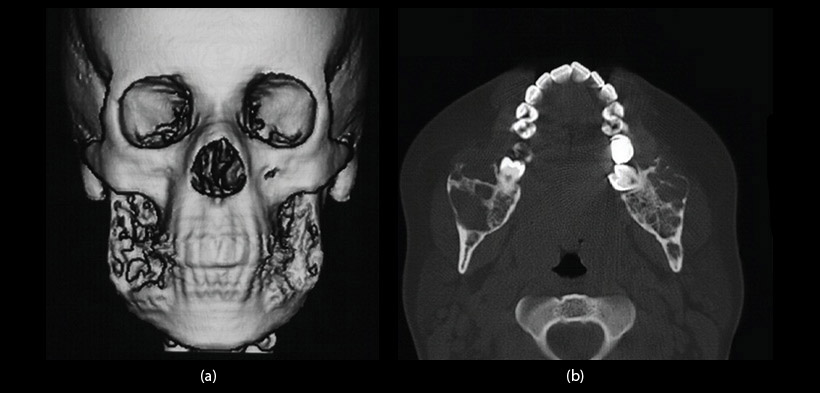

Fig. 2 A) Reconstrucción 3D de las imágenes de la TC, muestra el aspecto erosivo y múltiples depresiones en el hueso cortical vestibular bilateral de la región retromolar. B) vista axial de la TC, revela la imagen grande heterogénea con características expansivas e invasiva, la lesión es osteolítica, multilocular con perforación del hueso cortical en el ángulo y la rama de la mandíbula

Fig. 4 En la reconstrucción en 3D y en la vista axial de la TC, se muestra una regresión significativa de la lesión con hueso cortical se conserva en el ángulo y la rama de la mandíbula.